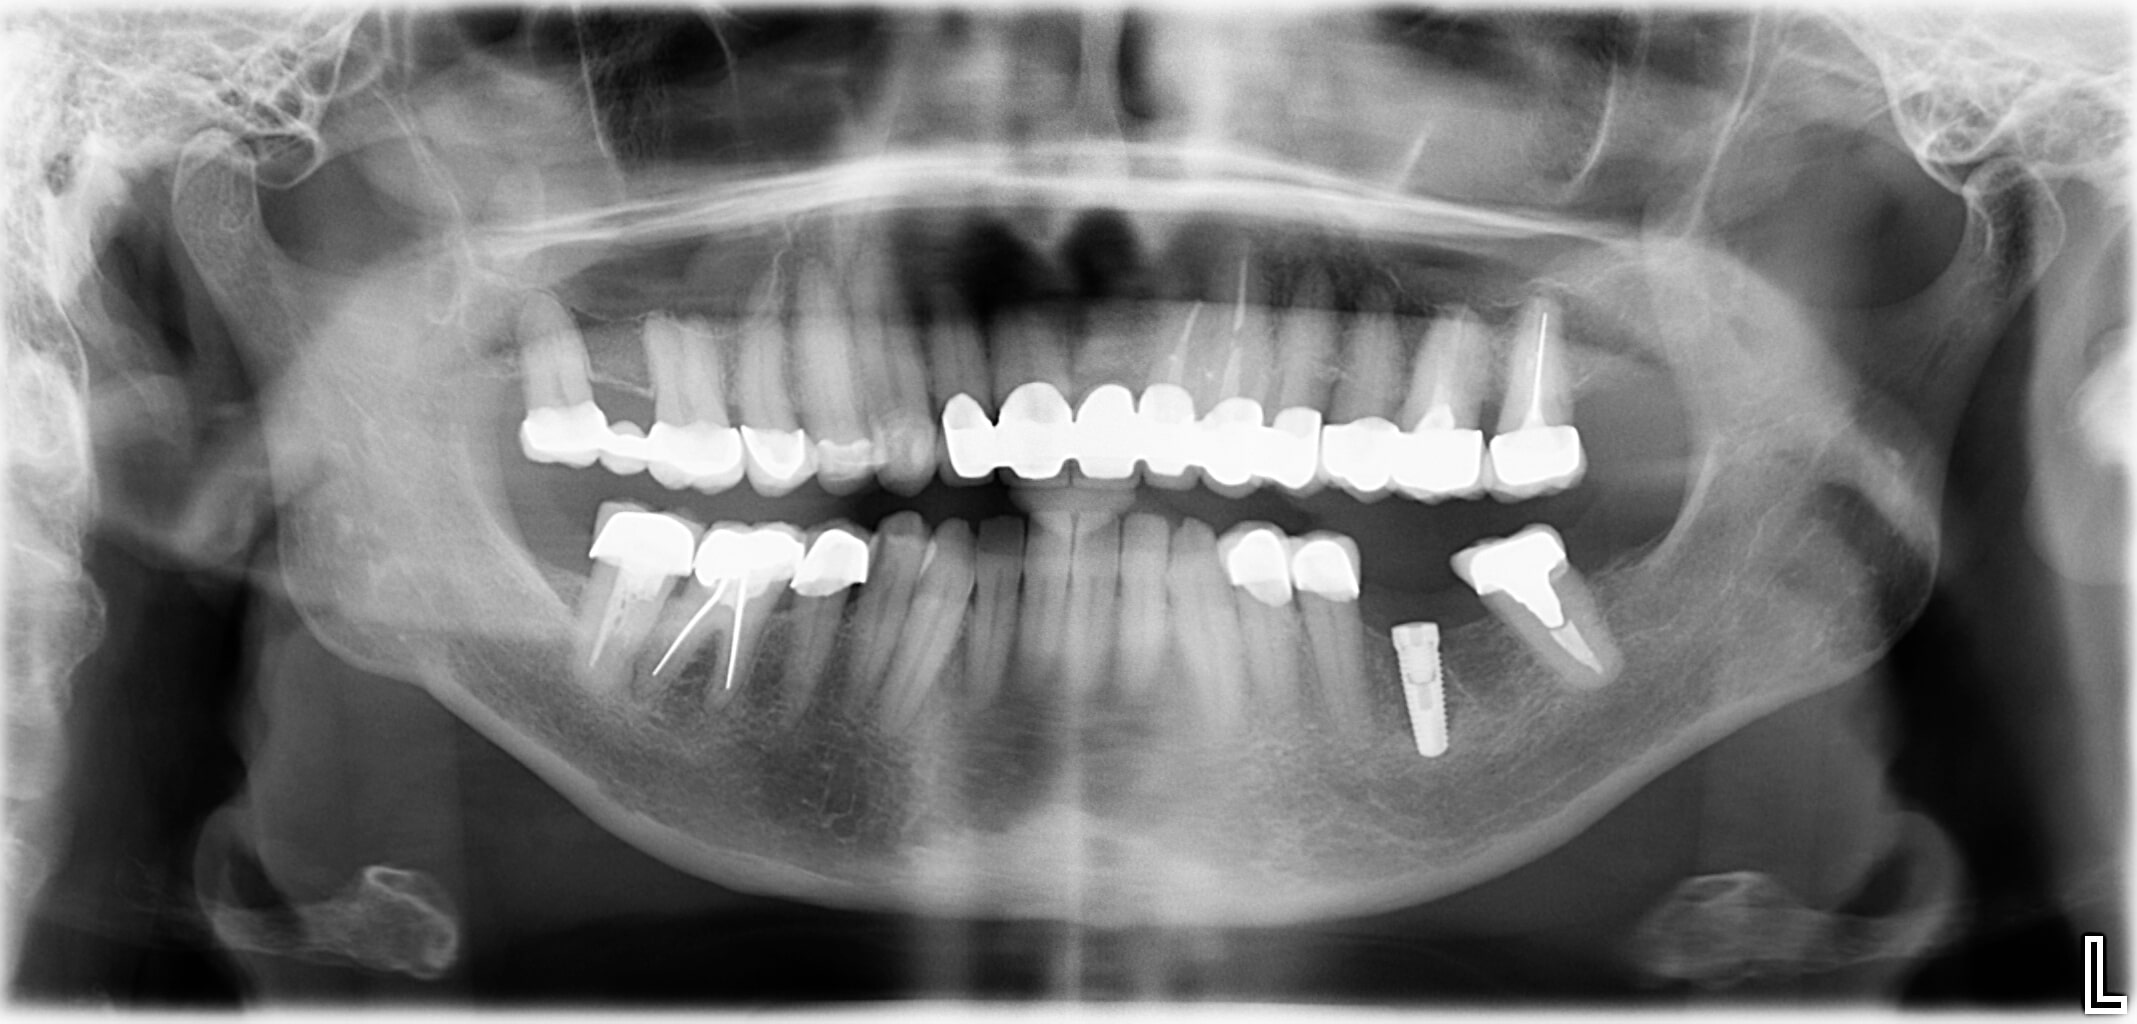

Wenn am Ende der Zahnreihe Zähne fehlen, muss eine herausnehmbare Prothese hergestellt werden. Für eine festsitzende Prothese wäre ein hinterer „Pfeiler“ zur Befestigung nötig. Durch den Einsatz von Implantaten kann man auf den herausnehmbaren Zahnersatz verzichten. Das bringt Vorteile beim Kauen und hilft bei der Vorbeugung funktioneller Gelenkerkrankungen.

- Am Ende der Zahnreihe fehlen ein oder mehrere Zähne

- Natürliche Zähne begrenzen den zahnlosen Abschnitt nur auf einer Seite

- Ein zahngetragener Zahnersatz (Brücke) ist nicht möglich

- Versorgung in der klassischen Zahnersatzkunde: Teilprothese abnehmbar

Die Lösung

- Eine rein implantatgetragene Verbundbrücke oder Einzelzahnimplantate vermeiden Brücken und abnehmbare Teilprothesen.

- Implantate als zusätzliche Pfeiler: Brücke auf natürlichen Zähnen und Implantaten